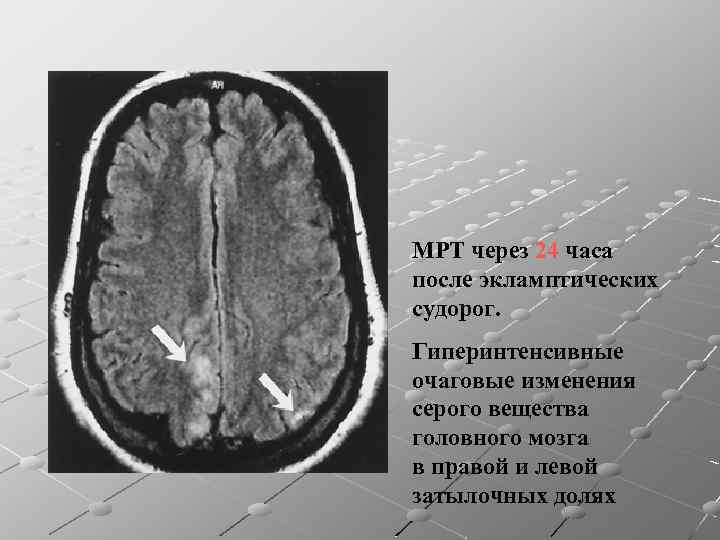

Иллюстрации и пояснения: гиподенсивный очаг на КТ головного мозга